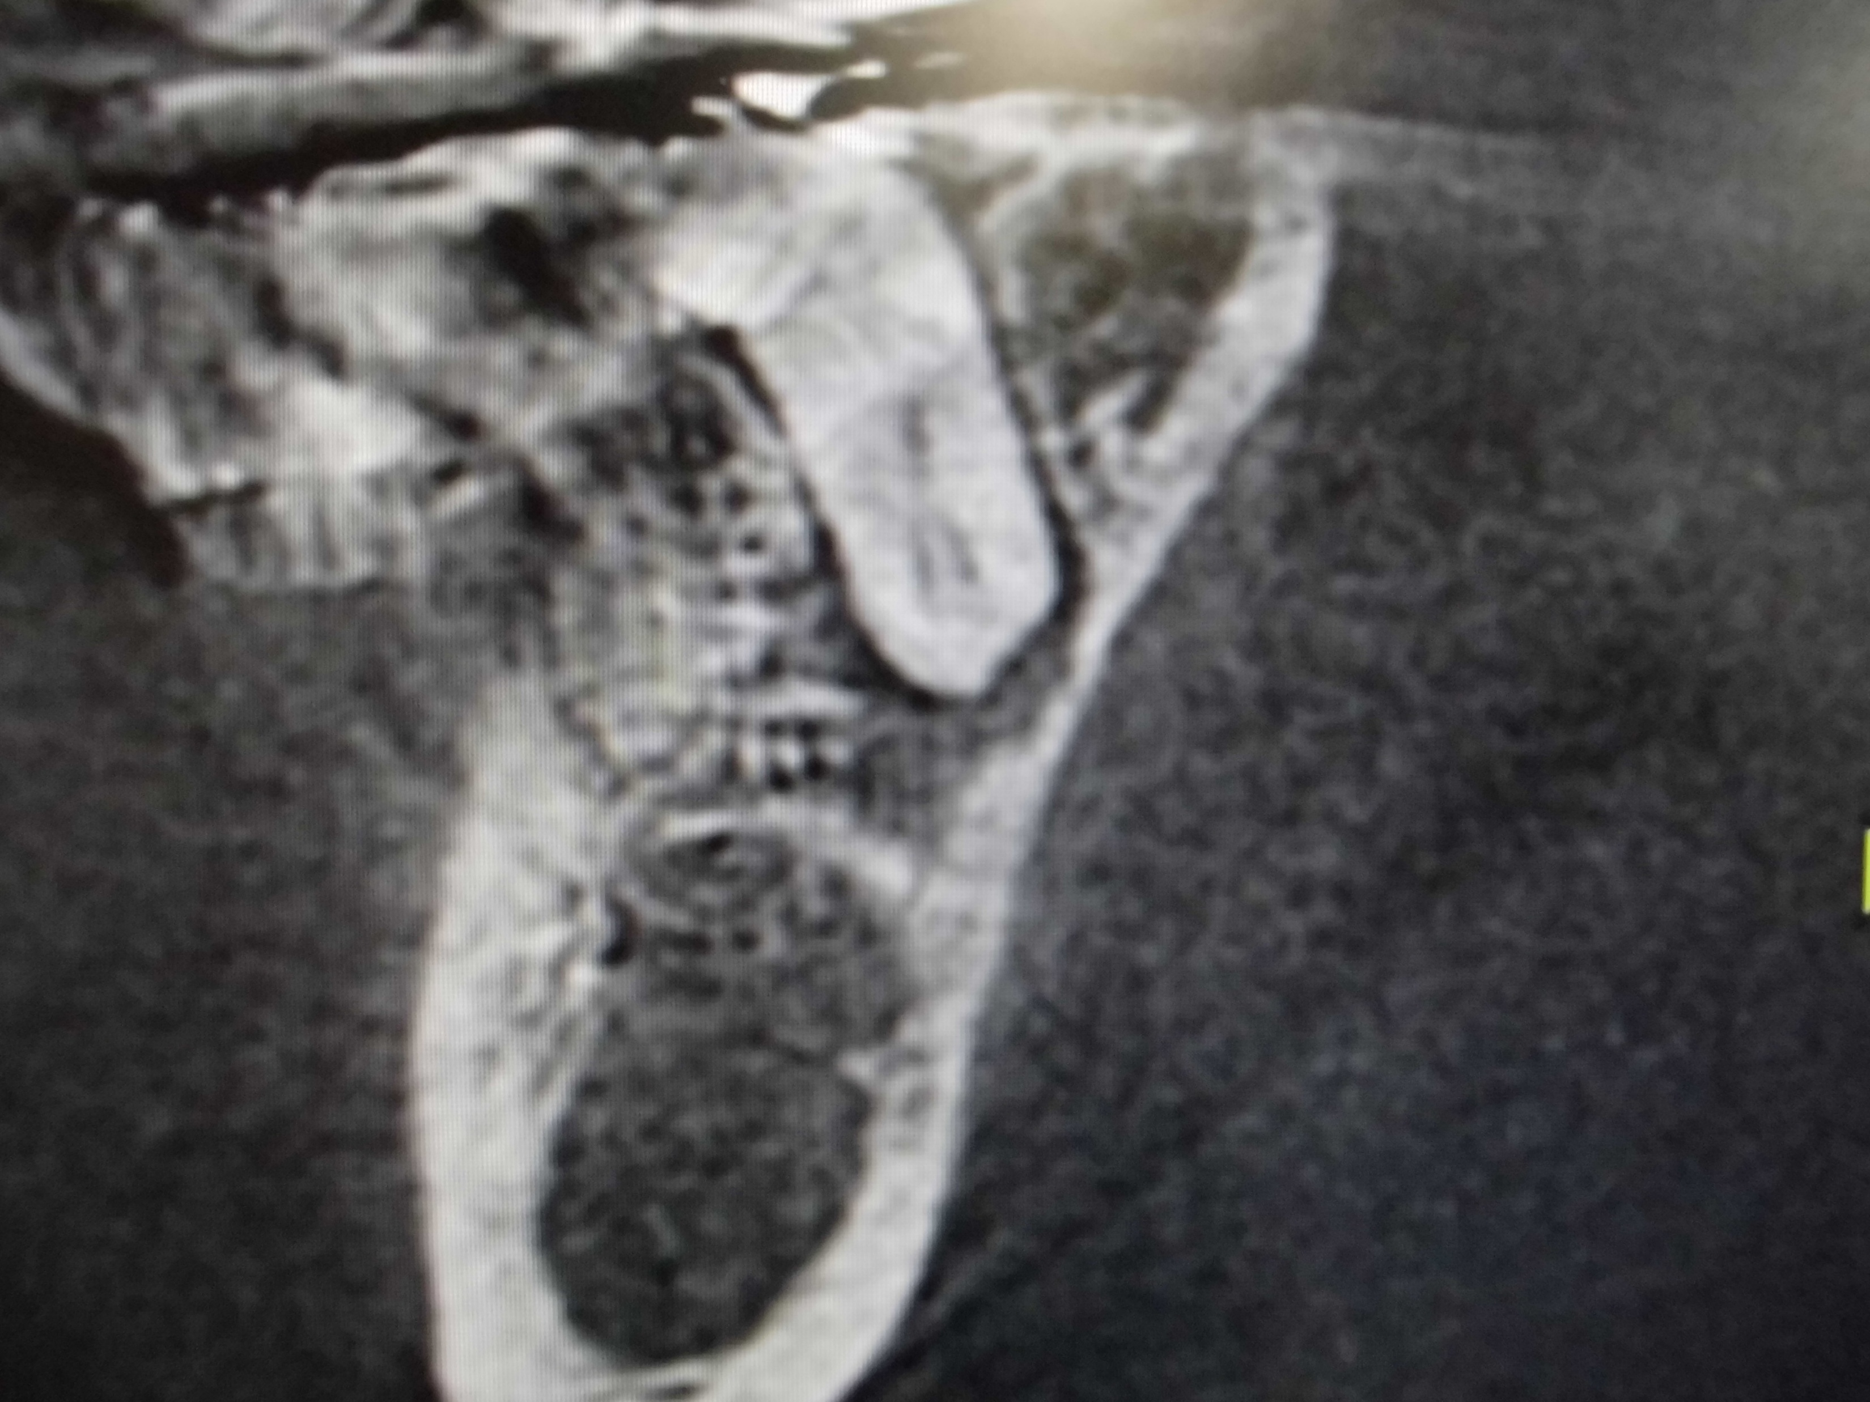

左上奥歯が割れています。一般的なレントゲンではわかりません。

CTでは破折線がはっきり見えます。患者様も納得しやすいです。